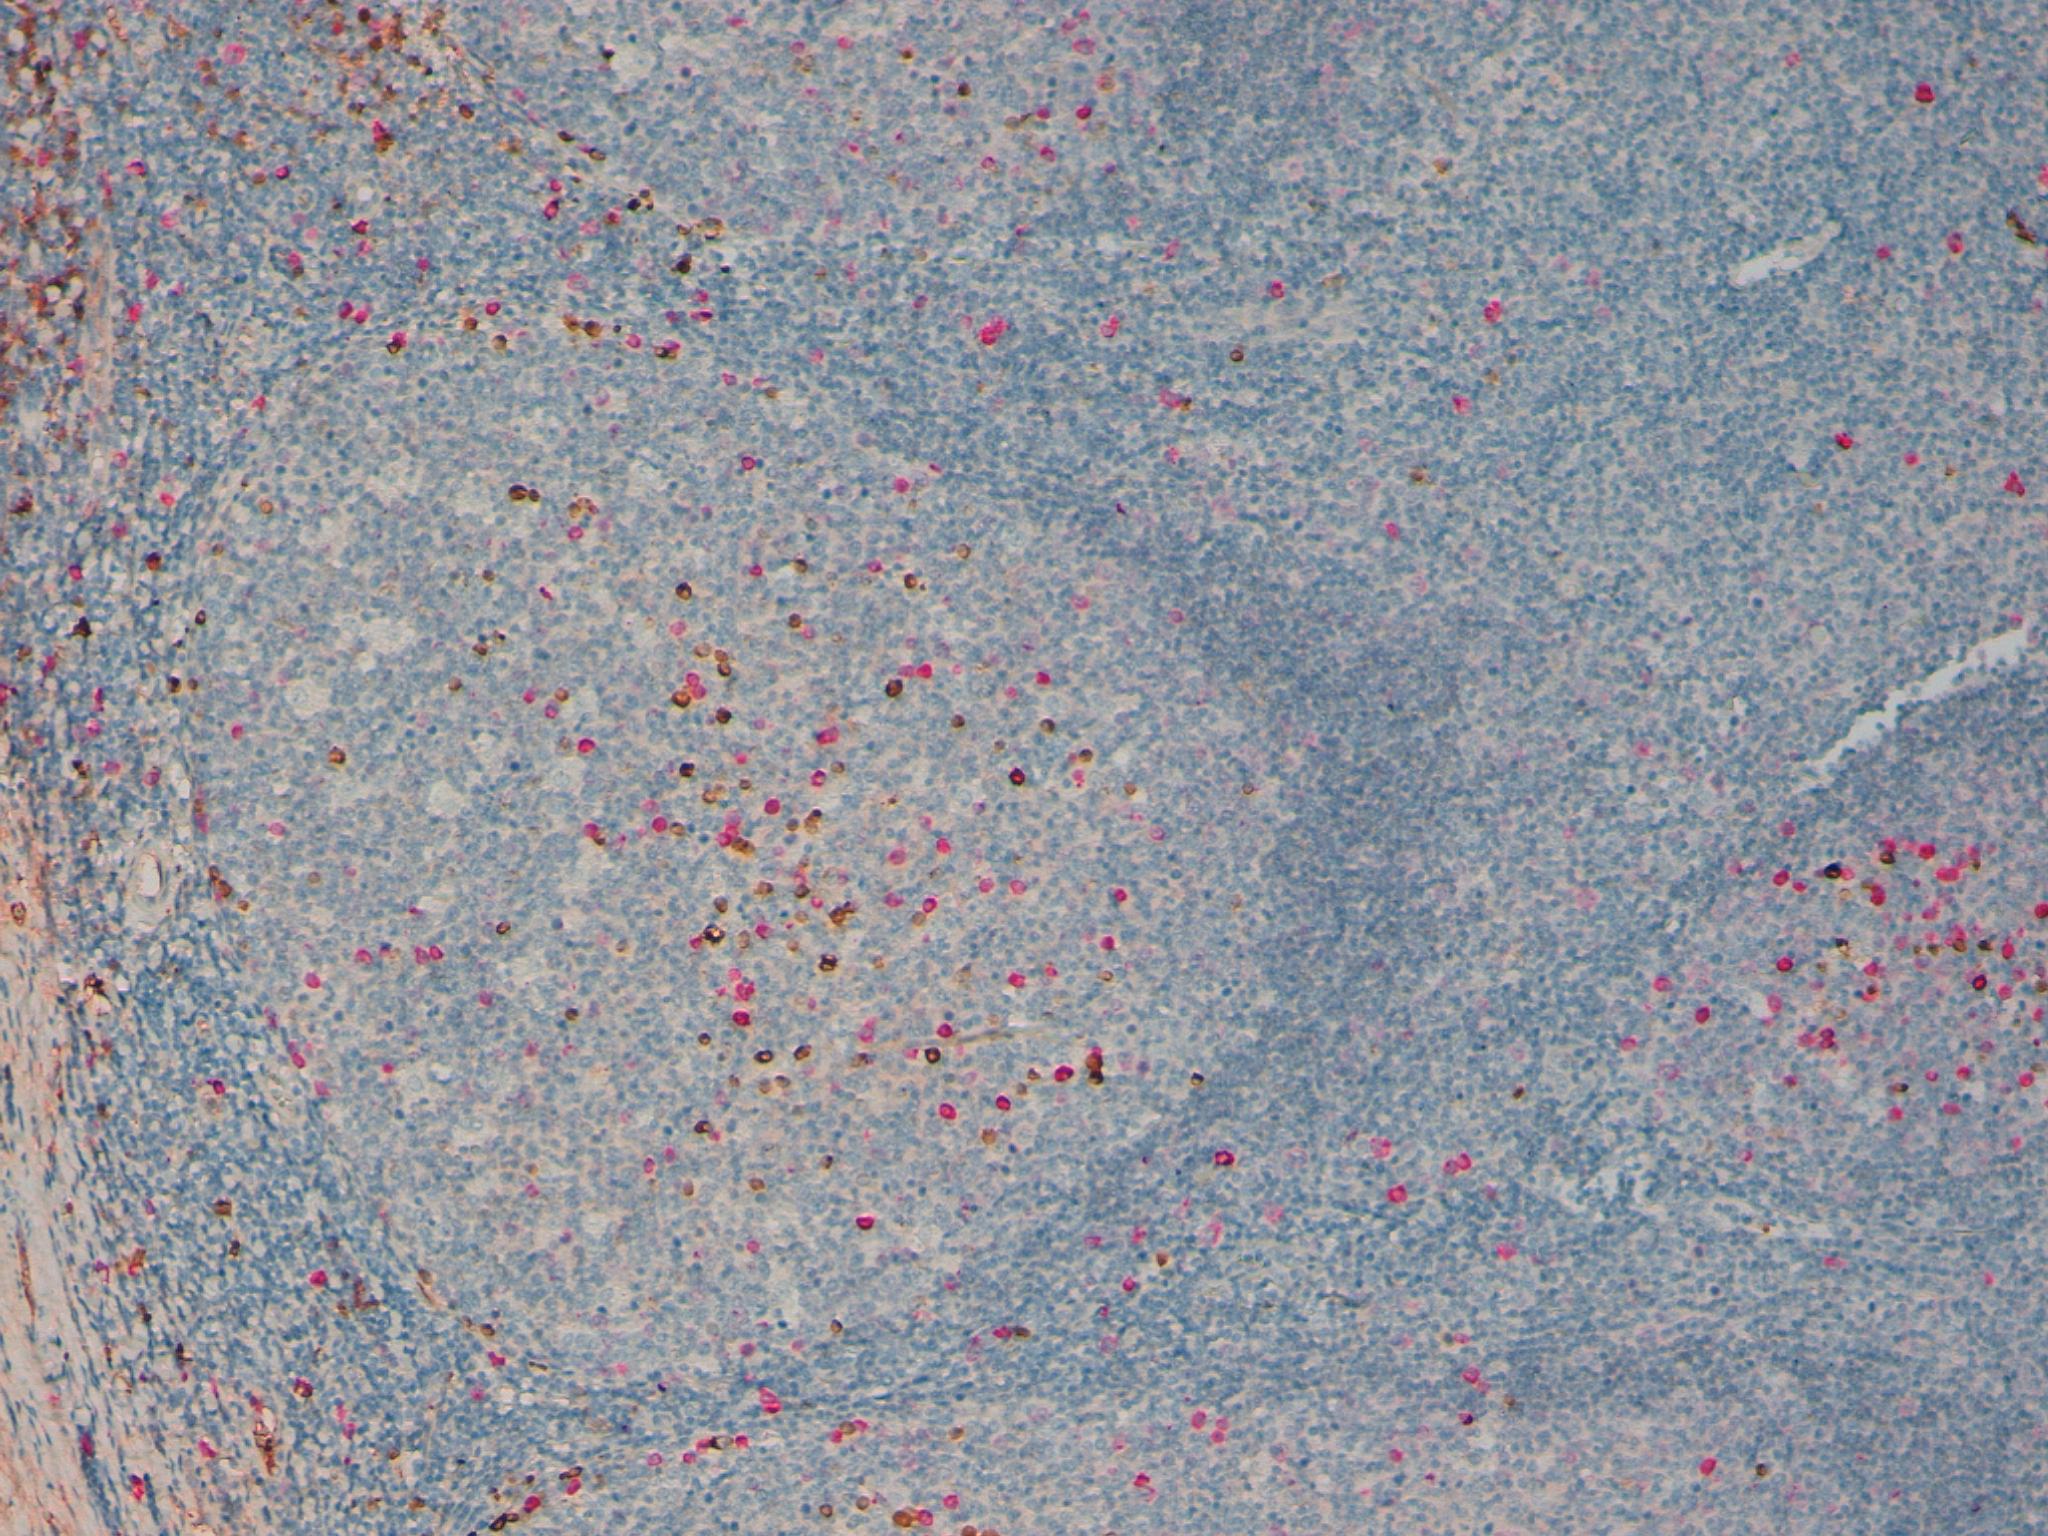

Multiplex IHC Staining: Human Lung CD68/cb-1 Single IHC Staining: Human Placenta, CD34

Kappa Lambda Double Staining 20x

Kappa Lambda Double Staining 10x